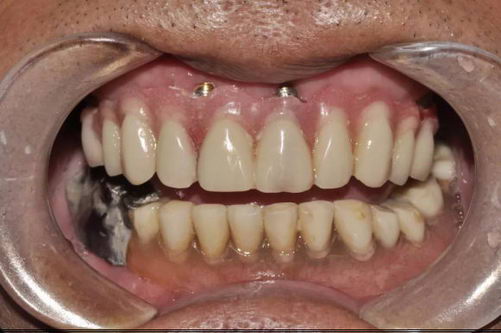

【种牙后,佩戴临时牙】

种植牙手术当天进行,大概30分钟后,再见到张叔叔只见他一脸笑容的说道“手术前还比较紧张,没想到过程这么快,而且很舒适,几乎没什么疼痛感,很轻松的就完成了种牙。”